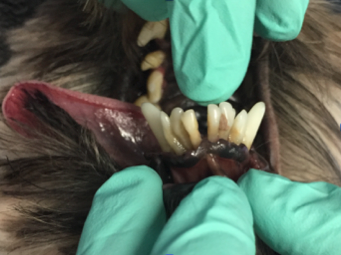

Als ich bei Leila ins Maul schaute, staunte ich schon nicht schlecht. Ich sah die Besitzerin an und fragte: „Wie alt war Leila noch mal?“ Leila war tatsächlich erst drei Jahre alt und doch wusste ich da schon, dass wir wahrscheinlich keinen Zahn retten könnten. Man sieht es wirklich nur, wenn man etwas genauer hinschaut: Leilas Zahnhälse lagen alle frei, und eitrige Beläge kamen aus der Tiefe des Zahnfachs (Abb. 2 - 5).

Solche Veränderungen treten oft bei einer hochgradigen Parodontitis auf. Eine Parodontitis ist die Entzündung des gesamten Zahnhalteapparates (also des Kieferknochens, des Zements, der Paradontalfasern und des Zahnfleischs) und wird durch die Bakterien, welche im Plaque enthalten sind, hervorgerufen. Diese zerstören die Anheftung der Gingiva am Zahn, und die Bakterien können bis zur Wurzel vordringen. Hier rufen sie Entzündungsreaktionen des Kieferknochens und der Gingiva hervor, wodurch beide sich zurückziehen und tiefe Paradontaltaschen entstehen lassen. Doch Leila hatte, wie auf den Bildern schön zu sehen ist, kaum Zahnstein oder Plaque.

Die Ursache hierfür ist eine vorangegangene Zahnreinigung, wobei die oberflächlichen Beläge der Kronen entfernt wurden, jedoch die Entzündung des darunterliegenden Gewebes nicht gesehen wurde.